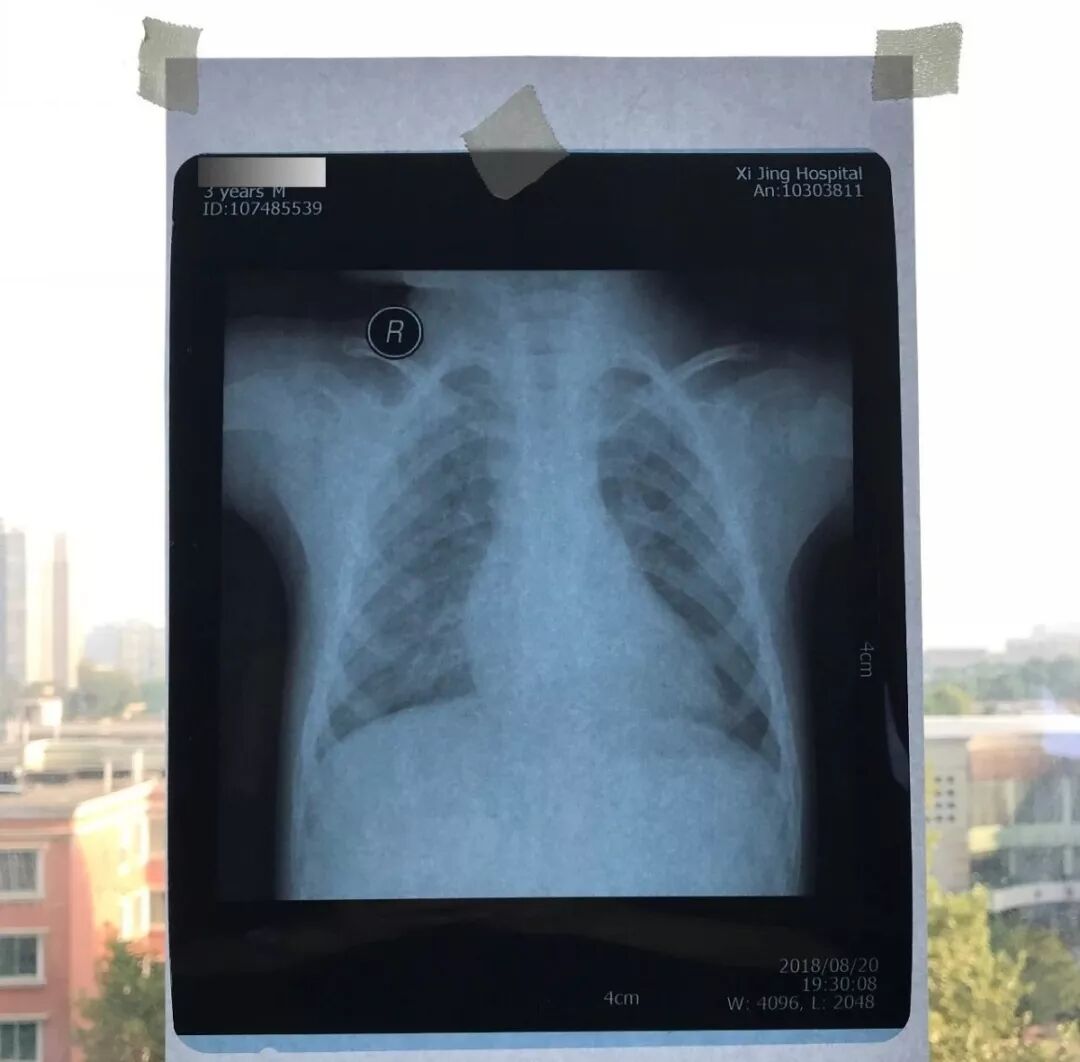

图11

医用阅片灯是什么专业科普!简单又实用的X线片翻拍技术,我只偷偷告诉你_https://www.jmylbn.com_新闻资讯_第16张

图12

医用阅片灯是什么专业科普!简单又实用的X线片翻拍技术,我只偷偷告诉你_https://www.jmylbn.com_新闻资讯_第17张

图13

医用阅片灯是什么专业科普!简单又实用的X线片翻拍技术,我只偷偷告诉你_https://www.jmylbn.com_新闻资讯_第18张

图14

拍片子时,如果一张片子上有两张图像的时候,合起来拍一张(图15),分开再各拍一张(图16,图17)